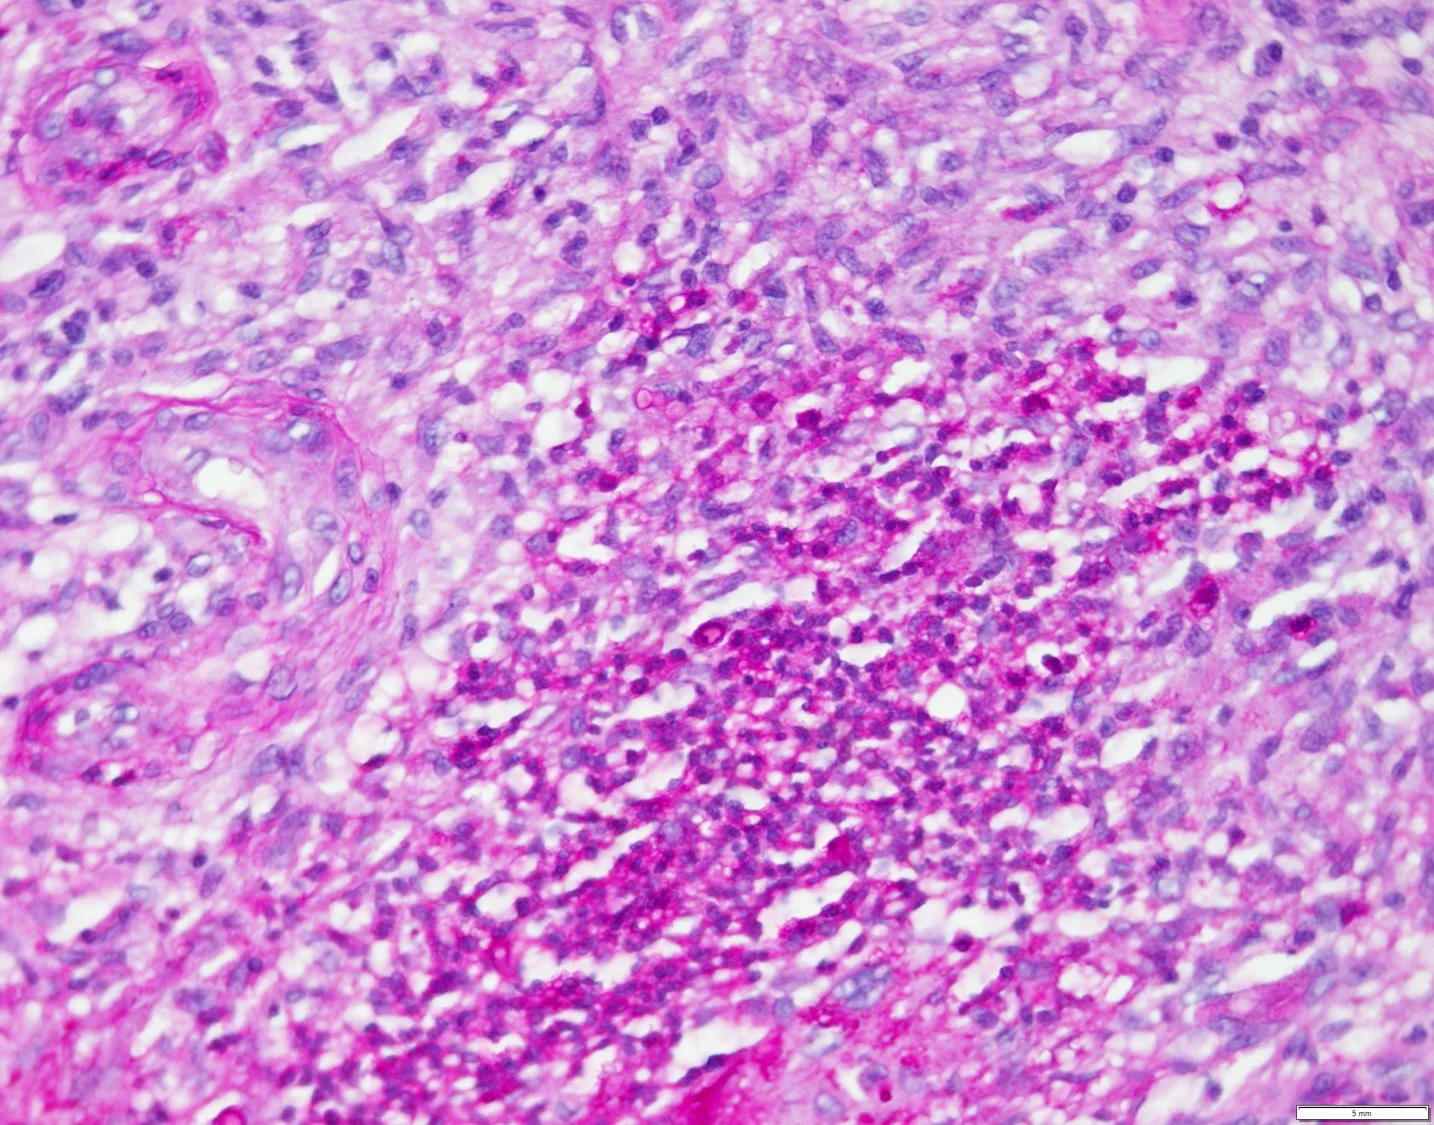

Case 4b: Leukemic Infiltrate Secondary to Chronic Myelogenous Leukemia

Caregivers: Carole Bitar, MD, Carole Bitar, MD; Jacqueline Witt, MS; Jalal Maghfour, MS; New Orleans, LA

History: This is a 45-year old woman with past medical history of chronic myelogenous leukemia (CML) on nilotinib that was admitted to the hospital for progressive swelling and severe pain of her left leg. The process started 6 days previously when she initially noticed a “knot” under her skin that was itchy then it became red and swollen. She experienced pain and burning sensation in that area. The patient noted that she experienced chills and subjective fever at home. She denied any trauma. Doppler ultrasound was unremarkable and there were no signs of DVT. She was started on clindamycin for presumed cellulitis and started to improve with decrease redness and swelling although there was a persistent subcutaneous nodule on the left leg. The subcutaneous nodule had a greenish discoloration. The patient reported that additional green subcutaneous nodules appeared on the right arm. She had a past history of leukemia cutis with abundant blasts in 2017 for which she was treated with induction chemotherapy. On this admission, she was started on hydroxyurea and nilotinib.

Current Medications: Clindamycin, hydroxyurea, nilotinib, pantoprazole.

Physical Examination: There is an erythematous plaque over the left shin, tender to touch and warm with a centrally located greenish subcutaneous nodule. Two subcutaneous greenish nodules over the right arm were present.

Laboratory Data: Two punch biopsies were performed over the left leg for hematoxylin and eosin stain and for flow cytometry. Laboratory work up was significant for very high WBC of 167x103. Bone marrow biopsy showed chronic myeloid leukemia with no blasts.

Histopathology: A punch biopsy showed an atypical perivascular infiltrate comprised of neutrophilic, eosinophilic, and mononuclear cells compatible with immature myelocytes involving the dermis and subcutis with hemorrhagic lobular panniculitis. The infiltrate was not blastic but was compatible with leukemic infiltrate secondary to chronic myelogenous leukemia. The majority of perivascular cells stained positive for CD68. Myeloperoxidase stained numerous cells compatible with myelocytes. ERG immunostain confirms the presence of endothelial cells.

Flow cytometry: Nucleated cellularity consists predominantly of granulocytic cells. While there is a minute population (1.6%) of CD34+ cells falling within a typical blast gate by CD45/side scatter, these do not form a discrete cluster on examined histograms. It is noted that this patient's prior cutaneous leukemia involvement reportedly manifested as a mixture of mature and immature cells; therefore, morphologic correlation is essential.

Clinical Course: The patient continues to be followed by hematology/oncology and maintain current medication regimen. She is hesitant to undergo the recommended induction chemotherapy.

Diagnosis: Leukemic infiltrate secondary to chronic myelogenous leukemia.